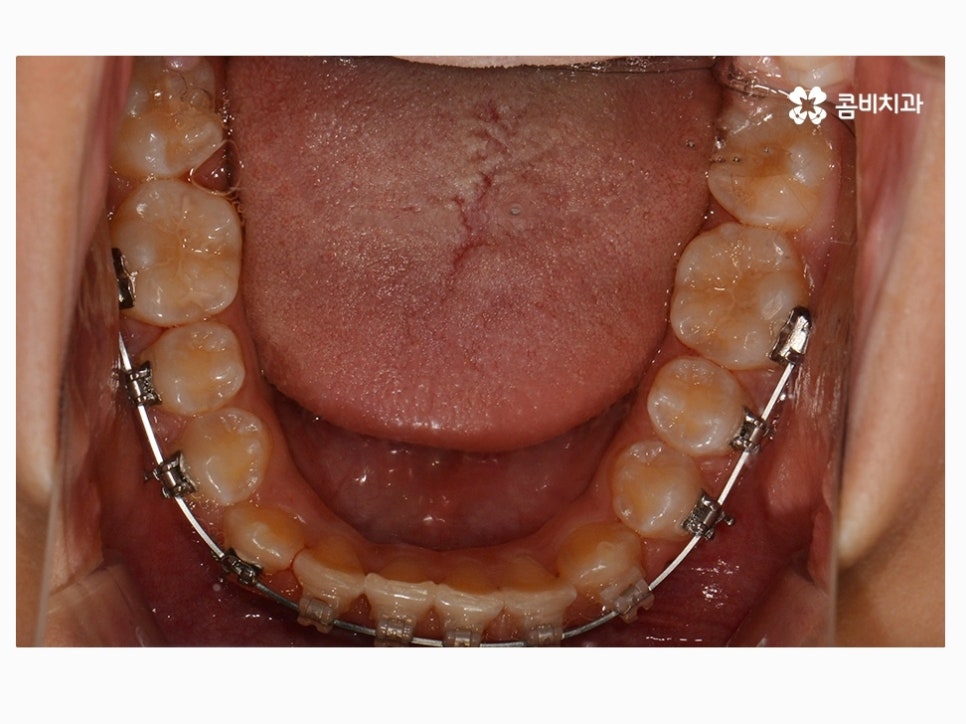

부정교합을 치료하는 방법은 나이대와 어떤 상태인지 진단에

따라서 달라질 수 있는데 위 케이스처럼 일반적인 치아교정으로

진행이 되는 경우도 있고 구외 교정 장치를 활용하는 경우 등 진단에 따라 다양할 수 있어요.